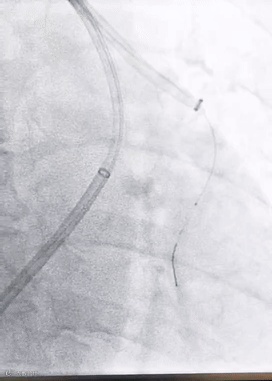

SWAM技术在下肢DVT中的应用:

8F天航抽吸导管与7mm天戟分离器完美配合,高效清除血栓。

导管+分离器,抽拉结合